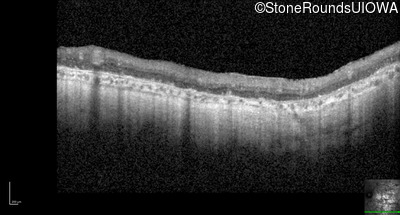

Optical Coherence Tomography - Left - Hand Motion sc

Exemplar / OCT Stack

OCT Stack